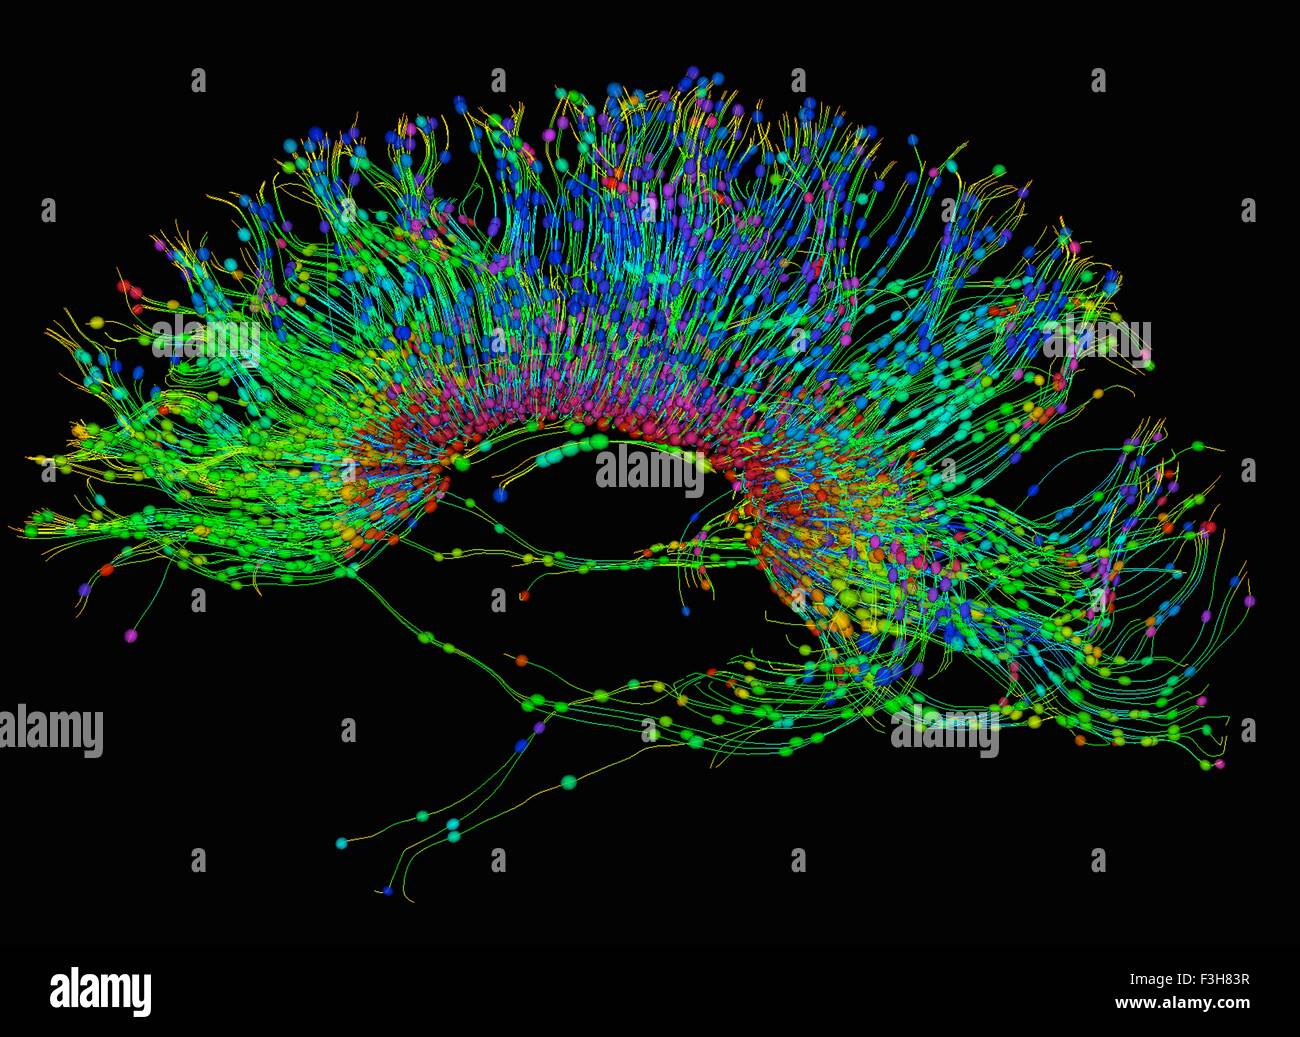

Diffusion tensor imaging (DTI) tractograpy. The color-coding of

Diffusion Tensor Imaging (DTI) - Fiber Tracking - Imagilys

Diffusion Tensor Imaging (DTI) - Fiber Tracking - Imagilys

Diffusion Tensor Imaging (DTI) - Fiber Tracking - Imagilys

Using Diffusion Tensor Imaging (DTI), axonal fiber tractography

Diffusion tensor imaging and fiber tractography | Radiology

A) Diffusion tensor imaging (DTI)-based whole-brain tractogram in